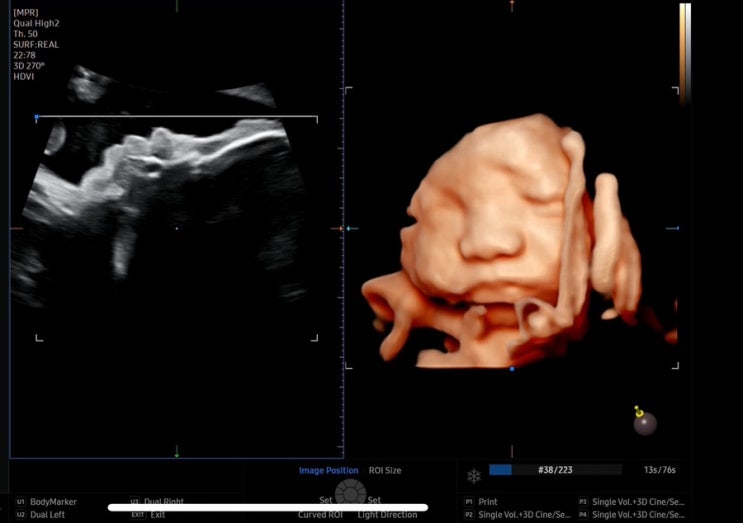

[임신 34주 후기] 많이 먹고 많이 돌아다닌 후기

임신 34주 후기 시작 ! 30주 이후로 정말 시간이 잘가는데 이 글을 쓰는 지금은 35주1일차이다! 인수인계해...